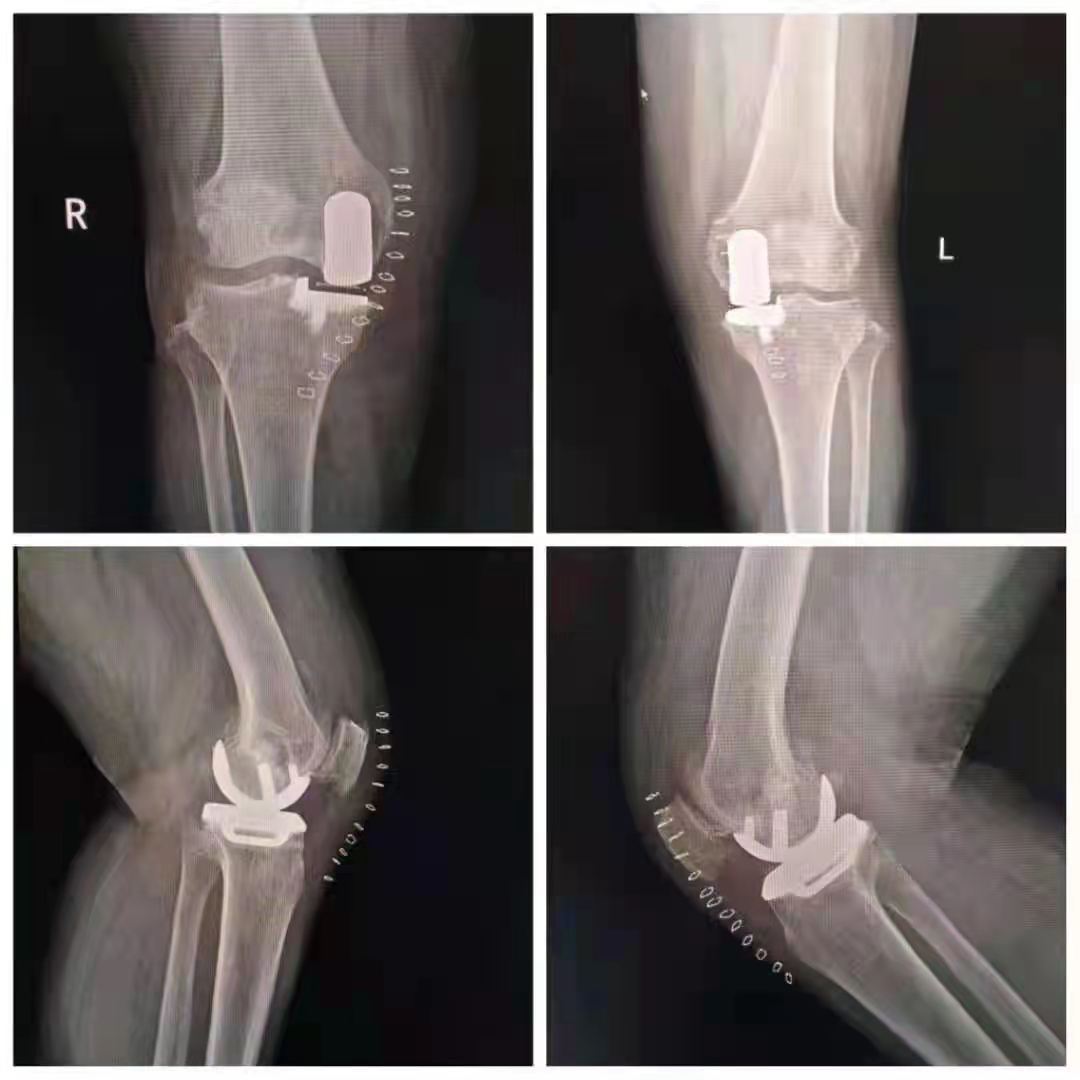

家住山亭區(qū)的王女士今年67歲。雙側(cè)膝關(guān)節(jié)疼痛多年,手術(shù)前已有加重現(xiàn)象,給生活帶來(lái)了很大不便。病魔帶來(lái)的痛苦讓他對(duì)未來(lái)失去了信心,農(nóng)活干不了,家務(wù)也不能操持,感覺(jué)自己像個(gè)廢人一樣。

幸運(yùn)的是,王女士慕名來(lái)到了山亭誠(chéng)德骨科醫(yī)院,專家檢查診斷,發(fā)現(xiàn)王女士雙側(cè)膝關(guān)節(jié)內(nèi)側(cè)磨損嚴(yán)重,外側(cè)部分和前后交叉韌帶上好,因此采取雙側(cè)同期部分置換。應(yīng)用牛津單髁活動(dòng)平臺(tái),手術(shù)屬于保膝范疇,保留了好的部分,修補(bǔ)了磨損重的部分,病人感受好,恢復(fù)快,功能好。如果錯(cuò)過(guò)這個(gè)修補(bǔ)的時(shí)機(jī),整個(gè)關(guān)節(jié)都磨損了,只能進(jìn)行全膝置換了。

術(shù)后,王女士恢復(fù)很好。疼痛癥狀完全消失,臉上也露出了久違的笑容。